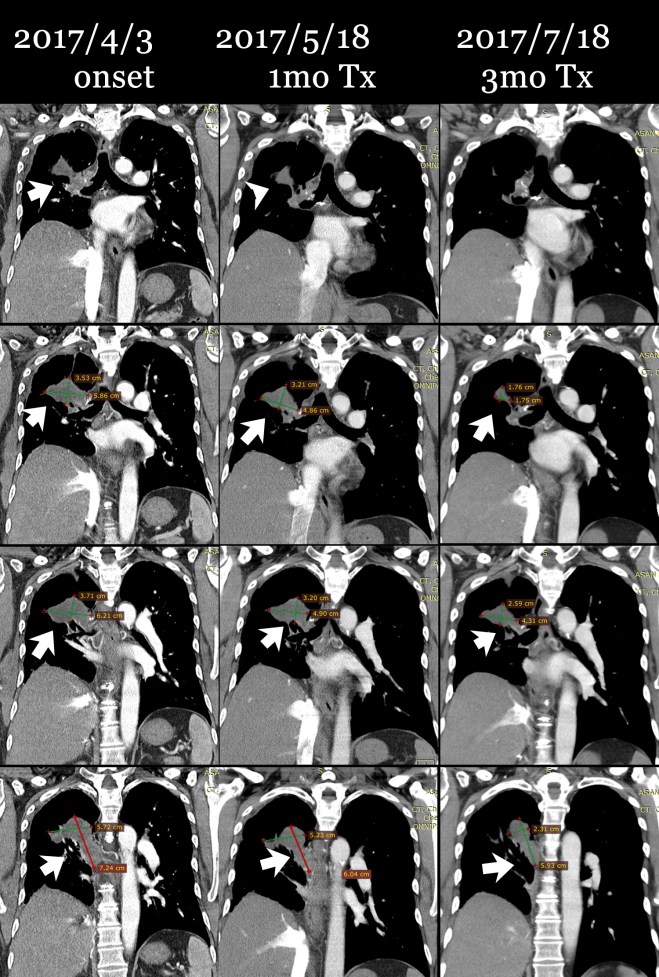

다음은 이 환자의 초기 2017년 4월 3일 CT와 이후 내원하여 4월 17일부터 한약 복용하고 한 달 뒤인 5월 18일 사진, 그리고 치료 3달 뒤인 7월 18일 사진을 coronal view (세운 채로 쪼갠 사진으로 앞에서 뒤로 단면이 cut된 사진)를 제시해 보면 확연히 종양이 줄어드는 것을 알 수가 있다. 그리고 또한 pleural thickening도 많이 감소된 것을 보게 된다. 비록 아산 소견서는 별 변화 없는것처럼 들었다고 하였지만 이 같은 차이가 쉽게 얻어지는 것은 아니며, 한약 양약 환자와 보호자의 노력이 합쳐져서 얻어지는 것임을 명심해야 한다.

다음 cut에서 확연히 우측 늑막의 pleural thickening이 줄어든 것을 볼 수 있다.

이 환자의 종양은 명확히 범주를 정하기에는 불규칙한 모양을 하고 있으나 대략 가장 크게 보이는 데를 기준으로 하여서 체적을 측정하면 (이는 전문가가 아닌 나의 측정이므로 오차가 꽤 있을 수는 있음을 양해를 구한다) 4월 3일 52CC 정도에서 한 달 치료 후에 35CC 정도로 감소되었고 또 7월 18일 마지막에는 18CC 정도로 줄었다고 볼 수 있다.